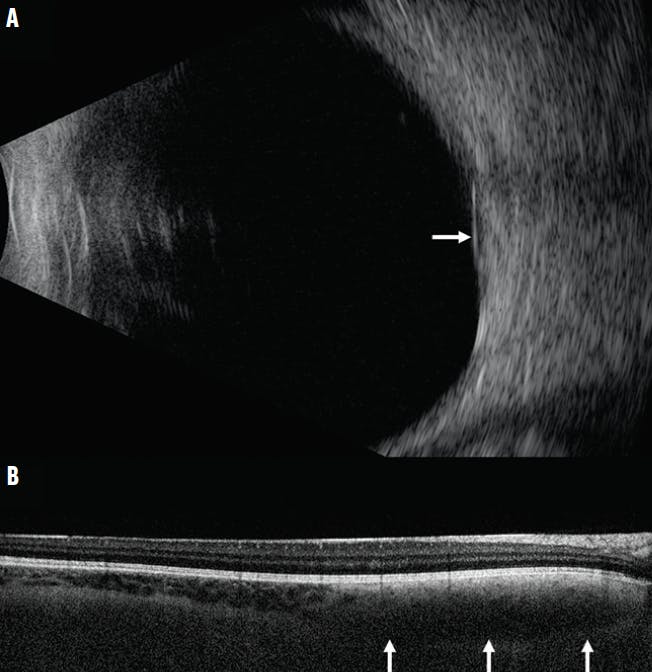

On examination, BCVA was 20/20 OU. The pupils, IOP, and anterior segment findings were within normal limits in each eye. The left fundus was unremarkable. The right fundus revealed a juxtapapillary pigmented choroidal mass measuring 7 mm in basal diameter, appearing approximately 1 mm larger than was documented 4 years prior (Figure 1B). Fundus autofluorescence (FAF) showed no areas of orange pigment or subretinal fluid (Figure 1C). Ultrasonography demonstrated a flat, dense choroidal mass with a thickness of 1.83 mm (Figure 2A). OCT showed an intact retina with no subretinal fluid (Figure 2B). Multimodal imaging revealed only one risk factor: diameter > 5 mm. A diagnosis of benign, slow enlargement of choroidal nevus was made, and observation was recommended.

<p>Figure 2. Ultrasonography of the right eye shows a flat, dense choroidal mass with thickness of 1.83 mm (arrow, A). OCT shows an intact retina with no subretinal fluid and the deep choroidal mass with loss of vascular markings (arrows, B).</p>

Figure 2. Ultrasonography of the right eye shows a flat, dense choroidal mass with thickness of 1.83 mm (arrow, A). OCT shows an intact retina with no subretinal fluid and the deep choroidal mass with loss of vascular markings (arrows, B).